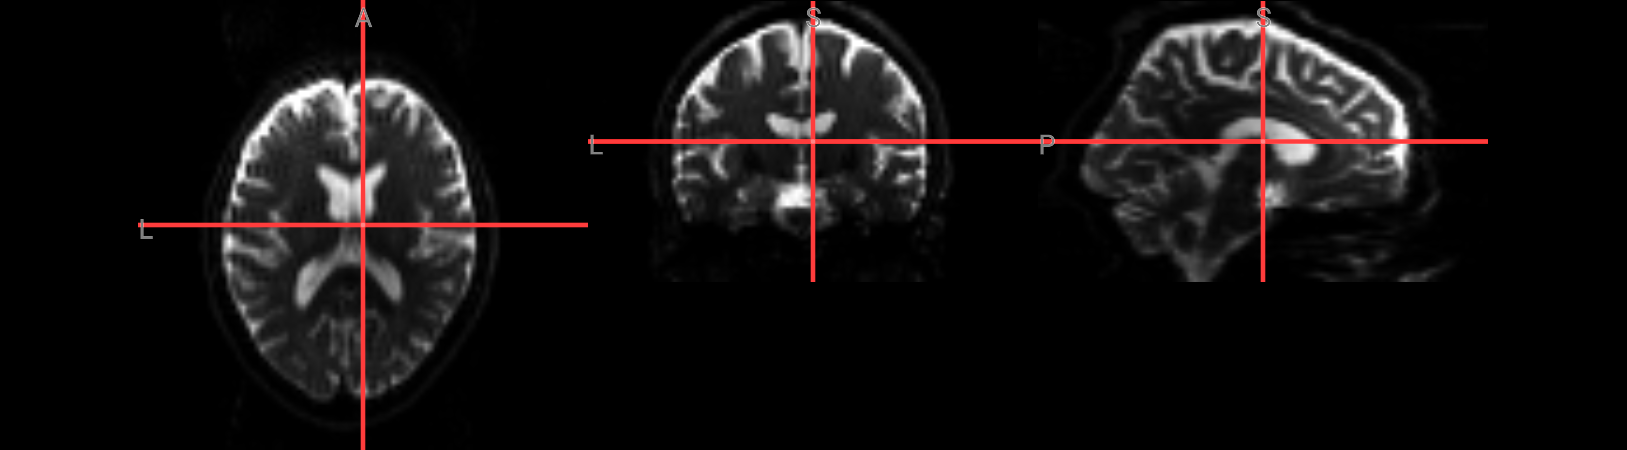

MRtrix’s dwi2mask

command works well in most scenarios. However, you can see from the above image that there are holes in the mask. You may be uninterested in these regions, but it is still a good idea to make sure the mask doesn’t have any holes anywhere.

plt.suptitle("Mask 'BET'")

plt.show()